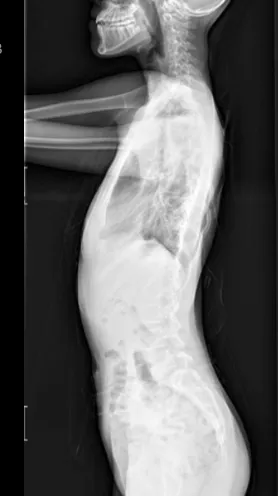

▷先天性脊柱畸形

先天性脊柱畸形,是指脊椎胚胎发育过程中,脊柱形成障碍或分节障碍所致的先天性脊柱畸形,包括侧凸、后凸和前凸,通常在婴幼儿期被发现。其中,半椎体畸形,尤其是完全分节的额半椎体,导致的脊柱侧凸保守治疗效果较差,早期诊断和手术治疗可避免严重的继发畸形,减少融合固定节段,保留更多的脊柱活动度,提高患儿生活质量。

▲ 女,3岁4个月,先天性脊柱侧弯半椎体畸形